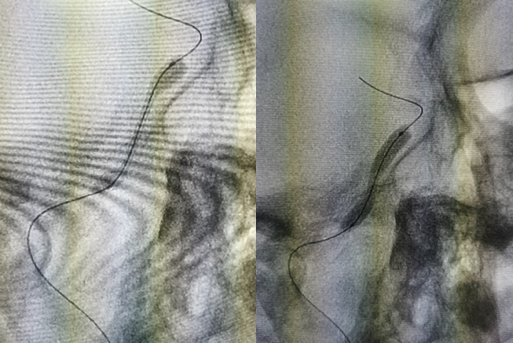

图7 Pilot结合SL-10通过C1开口质韧的闭塞段

图8 反复尝试无法顺利前进,Pilot在机化血栓内钻出一条路径

图9 反复尝试下微导管终于在岩骨段水平进入真腔